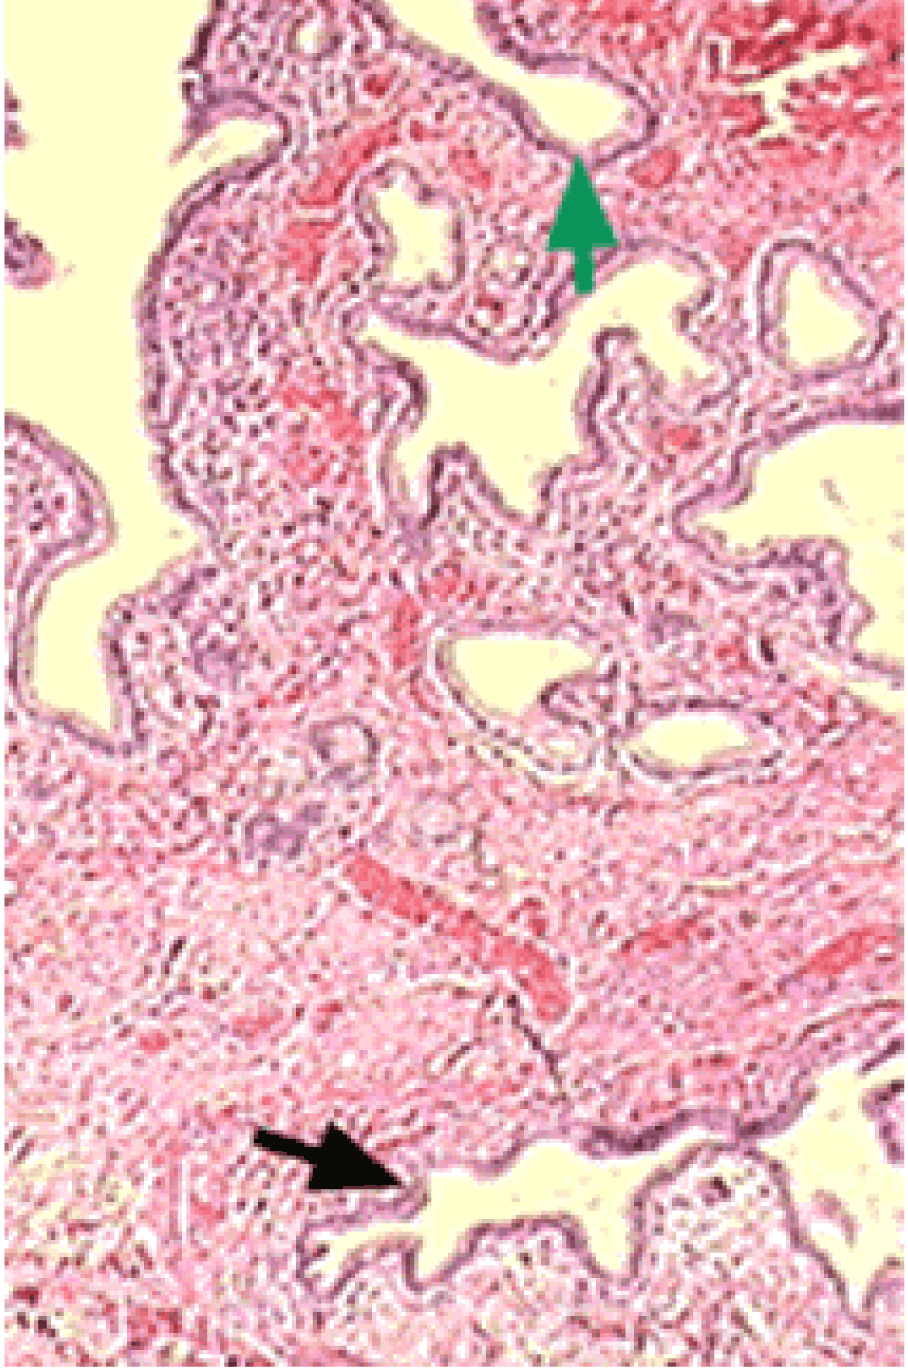

2. The length of the gallbladder was measured to be 25.8 cm. The measurement was made in the operation theatre, using a transparent straight ruler with centimeter markings on one side and inch markings on the other side. Microscopy showed normal histology of the gallbladder. (Figure 4)

Figure 4: Sections show normal histology of the gallbladder.